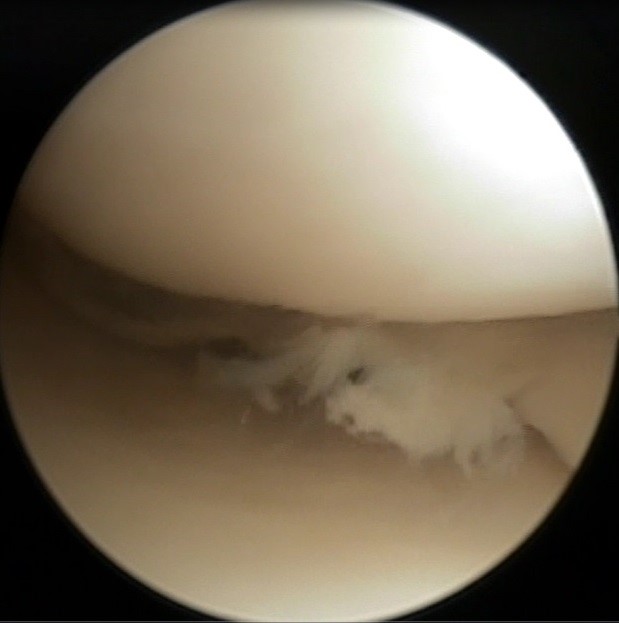

Upload Date: January 23, 2019 Full Size Image Dimensions: 619 × 623 Image Parent Post: Ρήξη Μηνίσκου

8.Αρθροσκοπική εικόνα σύμπλοκης ρήξ